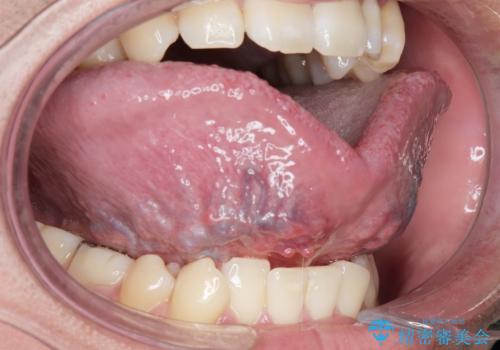

舌の可動範囲が広がり、満足していただけました。

舌小帯切除術は当日行うことができます。